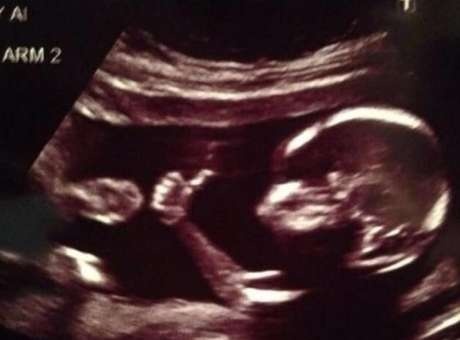

Foshnjat meshkuj gjuajnë më shumë se femrat

Sipas studimit të realizuar në Irlandë, meshkujt gjuajnë më shumë në shkelm kur janë në barkun e nënës dhe kjo e bën më të vështirë procesin e lindjes. Poashtu, koka e madhe e djemve shkakton komplikacione dhe probleme gjatë lindjes.